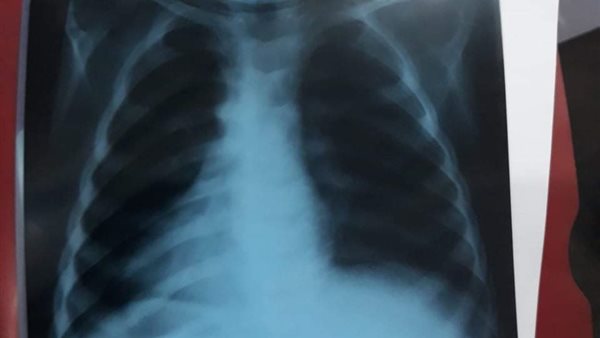

وذكر أحد الأطباء لـ"القاهرة 24" أن الطفل "أ، م، ز" وصل إلى المستشفى ويبلغ من العمر عامان ونصف، ونتيجة للكحة المستمرة والمُتعالية بشكل مثير، قرروا عمل أشعة عادية ثم مقطعية، ليتبين وجود جسم غريب في الرئة، وأثناء كحة الطفل خرج من فمه وسط حالة من الذهول بين الطاقم الطبي.